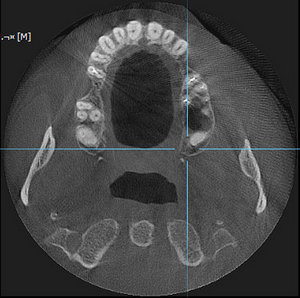

Под новый год заболела челюсть у виска справа (подозреваю, что на фоне проходящего гриппа). Сделал КТ челюсти. Специалистов у нас нет, предложили ехать за консультацией в краевой центр. Можно по снимку определить, что это у меня случилось?

Комментарий №175658 Комментарий №175658 Комментарий №175658 Комментарий №175658

• Описанная проблема может быть связана с височно-нижнечелюстным суставом. Возникнуть симптом может при дегенеративном поражении височно-нижнечелюстного сустава или вследствие других проблем в челюстно-лицевой области (патология прикуса, бруксизм, мышечный гипертонус). Рекомендуем Вам обратиться на консультацию к гнатологу или специалисту в области нейромышечной стоматологии